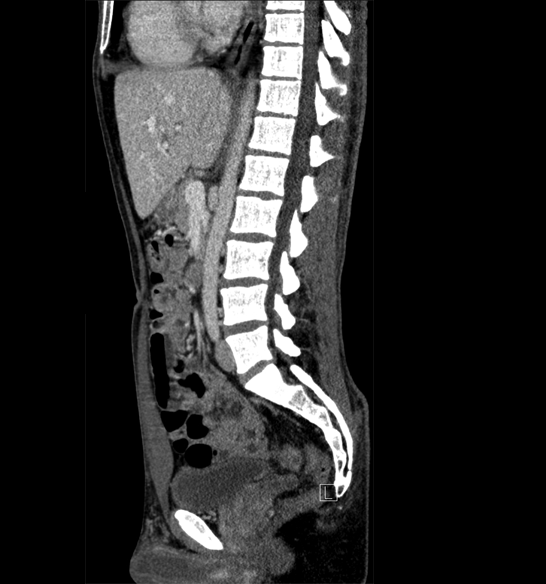

Body

Covers abdominal CT anatomy.